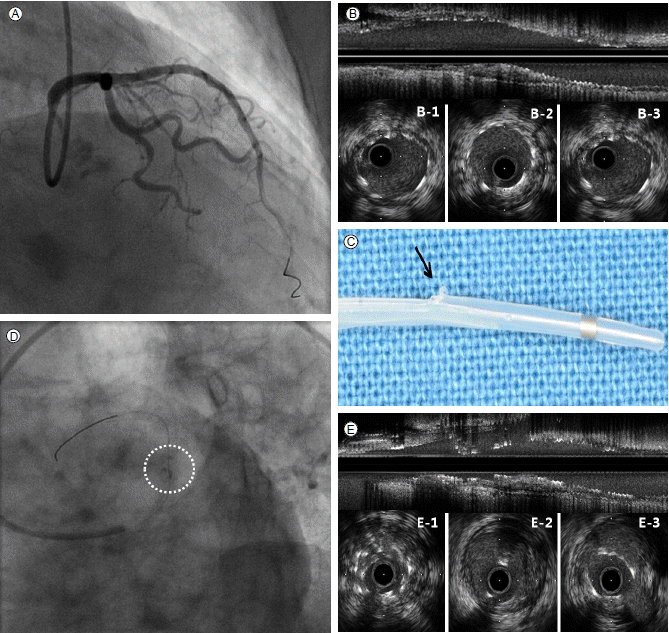

Figure 2.

(A) Post-stent intravascular ultrasound (IVUS), right anterior oblique cranial view. (B) Longitudinal IVUS images of the proximal left anterior descending artery (LAD) immediately following stent deployment. B-1: Stent proximal edge; B-2: Site of minimal stent area, 7.13 mm2; B-3: Stent distal edge. (C) Torn outer sheath tip of guidewire exit port during IVUS (arrow). (D) Post-IVUS retrieval angiogram with a dotted circle highlighting newly developed haziness. (E) Longitudinal IVUS images of the proximal LAD after forceful removal of the IVUS catheter. E-1: Stent-in-stent appearance; E-2: Stent fracture; E-3: Iatrogenic incomplete stent apposition.

74세 여자가 1개월 전부터 발생한 흉통을 주소로 본원에 내원하였다. 환자는 제2형 당뇨병을 진단받고 투약 중이었으며 그밖에 특이 병력, 과거력 및 가족력은 없었다. 심전도와 심초음파에서는 이상소견이 없었으나 심근 관류 단일 광자 방출 전산화 단층 촬영(single photon emission computed tomography, SPECT)에서는 좌전하행지 영역에 가역적인 병변이 있음을 확인하였다. 이후 시행한 관상동맥 조영술에서 좌전하행지의 근위부와 중간부에서 심한 협착 소견을 확인할 수 있었다(Fig. 1). 일차적으로 풍선 확장술을 시행하였고 3.5 × 15 mm, 2.75 × 14 mm zotarolimus 방출 스텐트(Endeavor resolute, Medtronic, Minneapolis, USA)를 좌전하행지의 근위부와 중간부에 각각, 중복(overlapping) 없이 12기압으로 확장하여 삽입하였다. 이후 관상동맥 조영술에서 최적의 결과를 얻었으며(Fig. 2A) 삽입된 스텐트를 평가하기 위해 혈관 내 초음파(intravascular ultrasound, IVUS)를 시행하였다. 혈관 내 초음파 카테터(Atlantis SR Pro, Boston Scientific Corporation, Boston, USA)를 좌전하행지의 원위부에 위치시킨 후 자동 후퇴를 하면서 영상을 얻었다. 그 결과 스텐트는 관상동맥 내에 적절하게 삽입되어 있었고, 불완전 확장(underexpansion) 소견은 관찰되지 않았다(Fig. 2B, 2B-1~2B-3). 이후 혈관 내 초음파를 수동으로 당겨내던 중 카테터의 끝부분(tip of IVUS)이 근위부의 스텐트 위치에 다다랐을 때 저항이 느껴졌다. 저자들은 일단 가이딩 카테터 및 유도철선, 초음파 카테터를 한꺼번에 조심스럽게 당겼으나 결국 초음파 카테터는 제거할 수 없었다. 그래서 일단 혈관내 초음파 카테터의 유연성을 높이기 위해 탐촉자(transducer)와 그것을 둘러싸고 있는 집(sheath)을 분리하고 탐촉자를 먼저 제거한 뒤 카테터 집을 당겼다. 이후 제거된 카테터 집의 끝(sheath tip of guidewire exit port)이 찢어진 걸 확인할 수 있었으며(Fig. 2C) 직후 시행한 조영술에서 근위부 스텐트 부분에 이전 조영에서는 보이지 않던 흐릿한 영상(haziness)을 관찰할 수 있었다(Fig. 2D). 이를 면밀히 관찰하고자 새로운 가이딩 카테터, 유도철선을 적절히 위치시킨 뒤 혈관 내 초음파를 시행하였으며 스텐트 내 스텐트 현상(stent in stent appearance; 스텐트의 완전 골절 이후 골절된 스텐트의 원위부가 근위부로 중첩되어 들어가는 현상, Fig. 2E-1), 스텐트 골절(stent fracture, Fig. 2E-2) 그리고 불완전 스텐트 부착(incomplete stent apposition, Fig. 2E-3)의 발생을 확인할 수 있었다. 이를 해결하기 위해 3.5 mm 크기의 풍선을 이용해 혈관 확장술을 시행한 뒤 4.0 × 24 mm zotarolimus 방출 스텐트(Endeavor resolute, Medtronic, Minneapolis, USA)를 이전 삽입한 근위부 스텐트에 중복하여 좌주간지 입구까지 삽입하였다. 이후 확인한 혈관 내 초음파에서는 스텐트가 혈관벽에 잘 부착되어 있음을 확인할 수 있었으며 조영술에서도 스텐트 변형은 더 이상 관찰할 수 없었다(Fig. 3). 환자는 다른 합병증 없이 퇴원하였으며 9개월 후 추적 관상동맥 조영술 및 혈관 내 초음파에서 스텐트가 잘 보존되어 있음을 확인할 수 있었다.